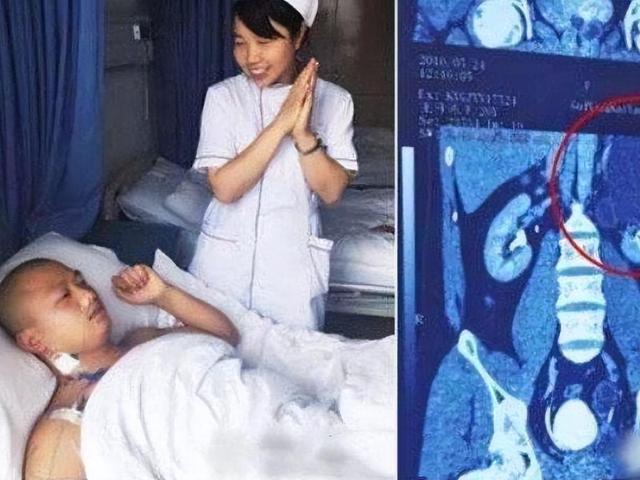

当这名男子出现在医院时,接诊医生在震惊的同时又羡慕不已,背地里夸他是“真男人”。医院的小护士们得知此事,纷纷前来围观。面对众人的疑问,男人的妻子微微一笑,骄傲地说:“他的身体素质很好!”

在那家三甲医院,王开炼又一次被确诊为“重复肾”,开始住院接受治疗。然而即便他每天打4针止痛针,疼痛还是没有得到丝毫缓解,反而更加严重了。

2016年6月15日,王开炼在手术室躺了四个半小时,终于被推了出来。面对站在手术室外焦急等待的妻子,梅医生淡定地说:“我们在他的腹部开了几个小孔,成功摘除了左上肾,手术相当成功!”

妻子终于放心下来,但让她没想到的是,丈夫住院恢复期间,医院的小护士们听得有人长了四个肾,纷纷前来围观。但大家若有所思地看着她时,她只好回应说:“我丈夫的身体素质的确很好。”